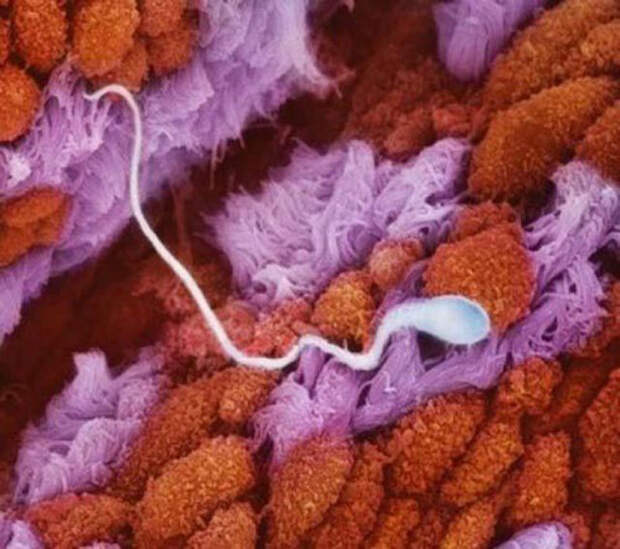

А это миллионы сперматозоидов направляются к шейке матки.  Дальше сперматозоид двигается по маточной трубе к яйцеклетке.

Дальше сперматозоид двигается по маточной трубе к яйцеклетке.  А это сама яйцеклетка, в ней сейчас зародится жизнь.